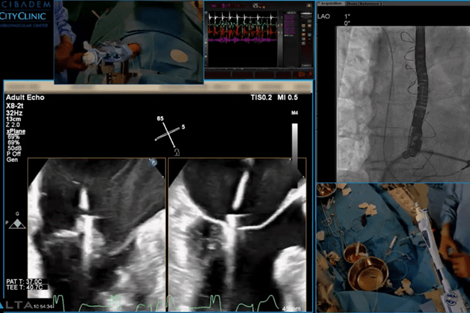

УМБАЛ Сърдечно-съдов център е сертифициран обучителен център за специалисти от Централна и Източна Европа

Проф. д-р Иво Петров и доц. д-р Зоран Станков проведоха практическо обучение за лекари от Румъния